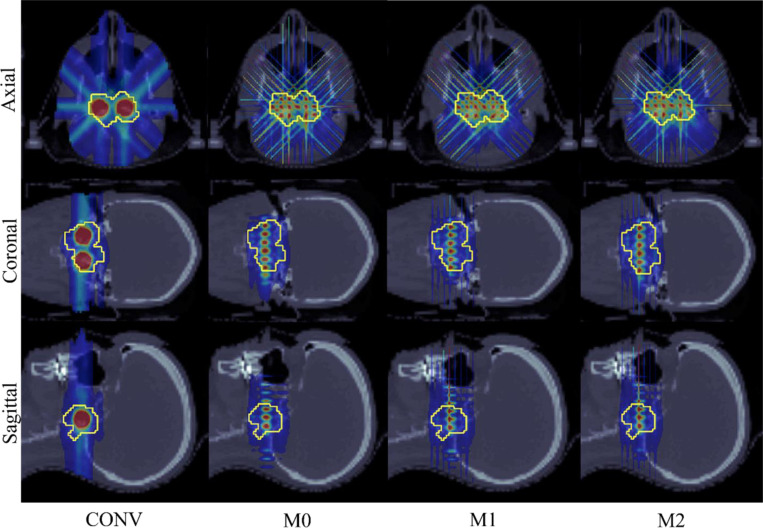

Methods: Three minibeam-pLATTICE methods are introduced. (1) M0: a fixed minibeam aperture orientation (e.g., 0°) for all beam angles; (2) M1: alternated minibeam aperture orientations (e.g., between 0° and 90°), for consecutive beam angles; (3) M2: multiple minibeam aperture orientations (e.g., 0° and 90°) for each beam angle. The purpose of M1 or M2 is to correct anisotropic dose distribution at lattice peaks due to the planar spatial modulation of minibeams. For each minibeam-pLATTICE method, an optimization problem is formulated to optimize dose uniformity in target peaks and valleys, as well as dose-volume-histogram-based objectives. This optimization problem is solved using iterative convex relaxation and alternating direction method of multipliers (ADMM).

Results: Three minibeam-pLATTICE methods are validated to demonstrate the feasibility of minibeam-pLATTICE for two clinical head-and-neck (HN), one abdominal and one brain case. The advantages of this modality over conventional beam (CONV) pLATTICE are evaluated by comparing peak-to-valley dose ratio (PVDR) and dose delivered to organs at risk (OAR). All three minibeam-pLATTICE modalities achieved improved plan quality compared to CONV, with M2 yielding the best results. For instance, in one HN case, the following improvements were observed: PVDR increased to 3.73 (M2), compared to 3.27 (CONV), 3.72 (M0), and 3.49 (M1), while the mean dose to the mandible was reduced to 0.18 Gy (M2), compared to 0.33 Gy (CONV), 0.17 Gy (M0), and 0.14 Gy (M1).